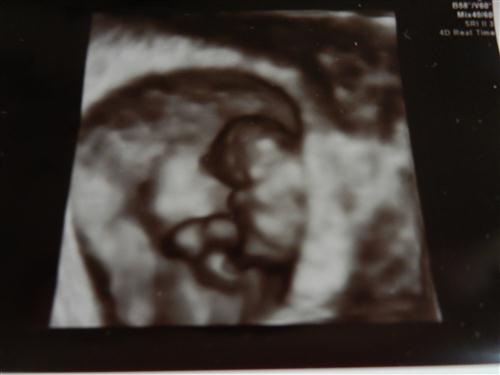

I had a 3d sonogram today! It was only supposed to be a 2d to just make sure everything is ok since my doctor's office is being really stingy with the sonograms. Everything is great! It was so cute and s/he was covering his/her little face.

So cute! Your baby's in hiding too.  Great pic!!

so here's my baby bean that's already giving me grey hairs at 8w4d thank god everything looked ok yesterday after the scare with the bright red bleeding on Sunday night. At least I got to see little bean before my next appointment at 10 weeks, you can see the head is tucked into the arms which are still developing